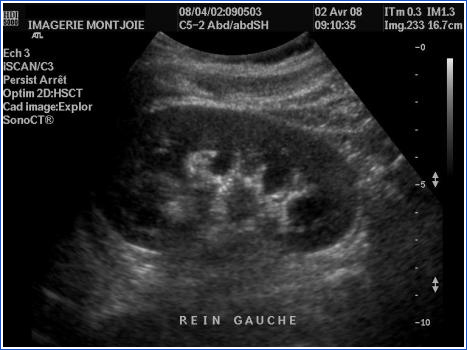

Bilan d’une insuffisance rénale chez un patient: comment est le rein?

petit, avec dédifférenciation cortico-médullaire => en faveur d’une maladie rénale chronique